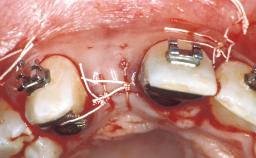

In February 2005, a 25-year-old female patient, a nonsmoker, was referred to our clinic due to tooth 11 presenting a chronic fistula following unsuccessful root-canal treatment and several attempts at endodontic surgery. The dental history revealed that more than ten years earlier, teeth 11 and 21 had been traumatized during a sports accident. Consequently, 11 had lost its vitality, and there were two moderate fractures of the mesioincisal borders of the two central incisors that had been restored with direct composite restorations. At the time of examination, the composite restorations showed signs of wear, some discoloration, and marginal infiltration. The patient also complained about a moderate discoloration of the clinical crown of the non-vital tooth 11. The patient was in good general health, and her medical history revealed no significant findings.